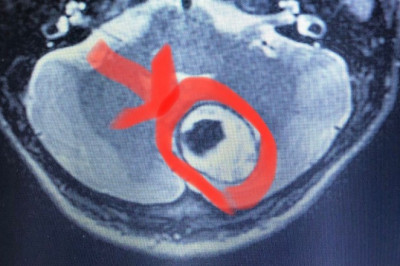

Yalova Devlet Hastanesi, bir ilke daha imza atarak Beyin Cerrahi Dr. Ali Rıza Özcan tarafından Nöronavigasyon-Mikro Cerrahi yöntemi ile beyincik tümör...